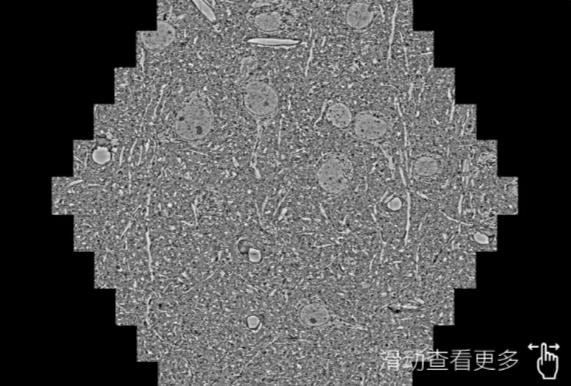

鼠脑切片。左图使用台州蔡司台州扫描电镜MultiSEM706对165μmx143pm面积区域成像,耗时仅需1.5秒。右图为鼠脑切片中30μm区域放大效果。样品由芝加哥大学B.Kasthuri提供。

使用蔡司高速台州扫描电镜MultiSEM对1mm²人脑皮层组织进行高分辨成像,并对其中的各种细胞结构进行三维重构分析。左图展示了2x3mm²组织平面中锥体神经元的三维重构效果。右图显示了局部体积神经元三维重构。图像由哈佛大学chtman实验室提供,渲染图由D. Berger 制作。